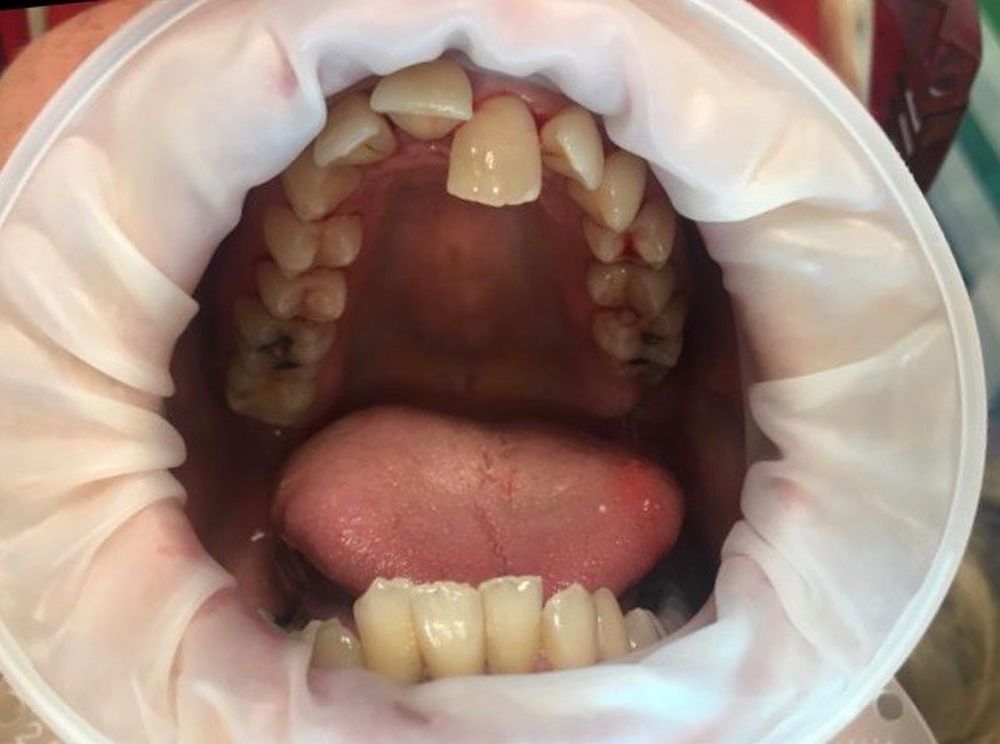

- Orthodontic TreatmentsAn underbite occurs when the lower teeth extend further than the upper teeth, creating what is also known as a reverse bite.

While mild underbites may only affect your appearance, severe cases can affect your chewing, speech, and overall oral health.

- Lower teeth that protrude past the upper teeth